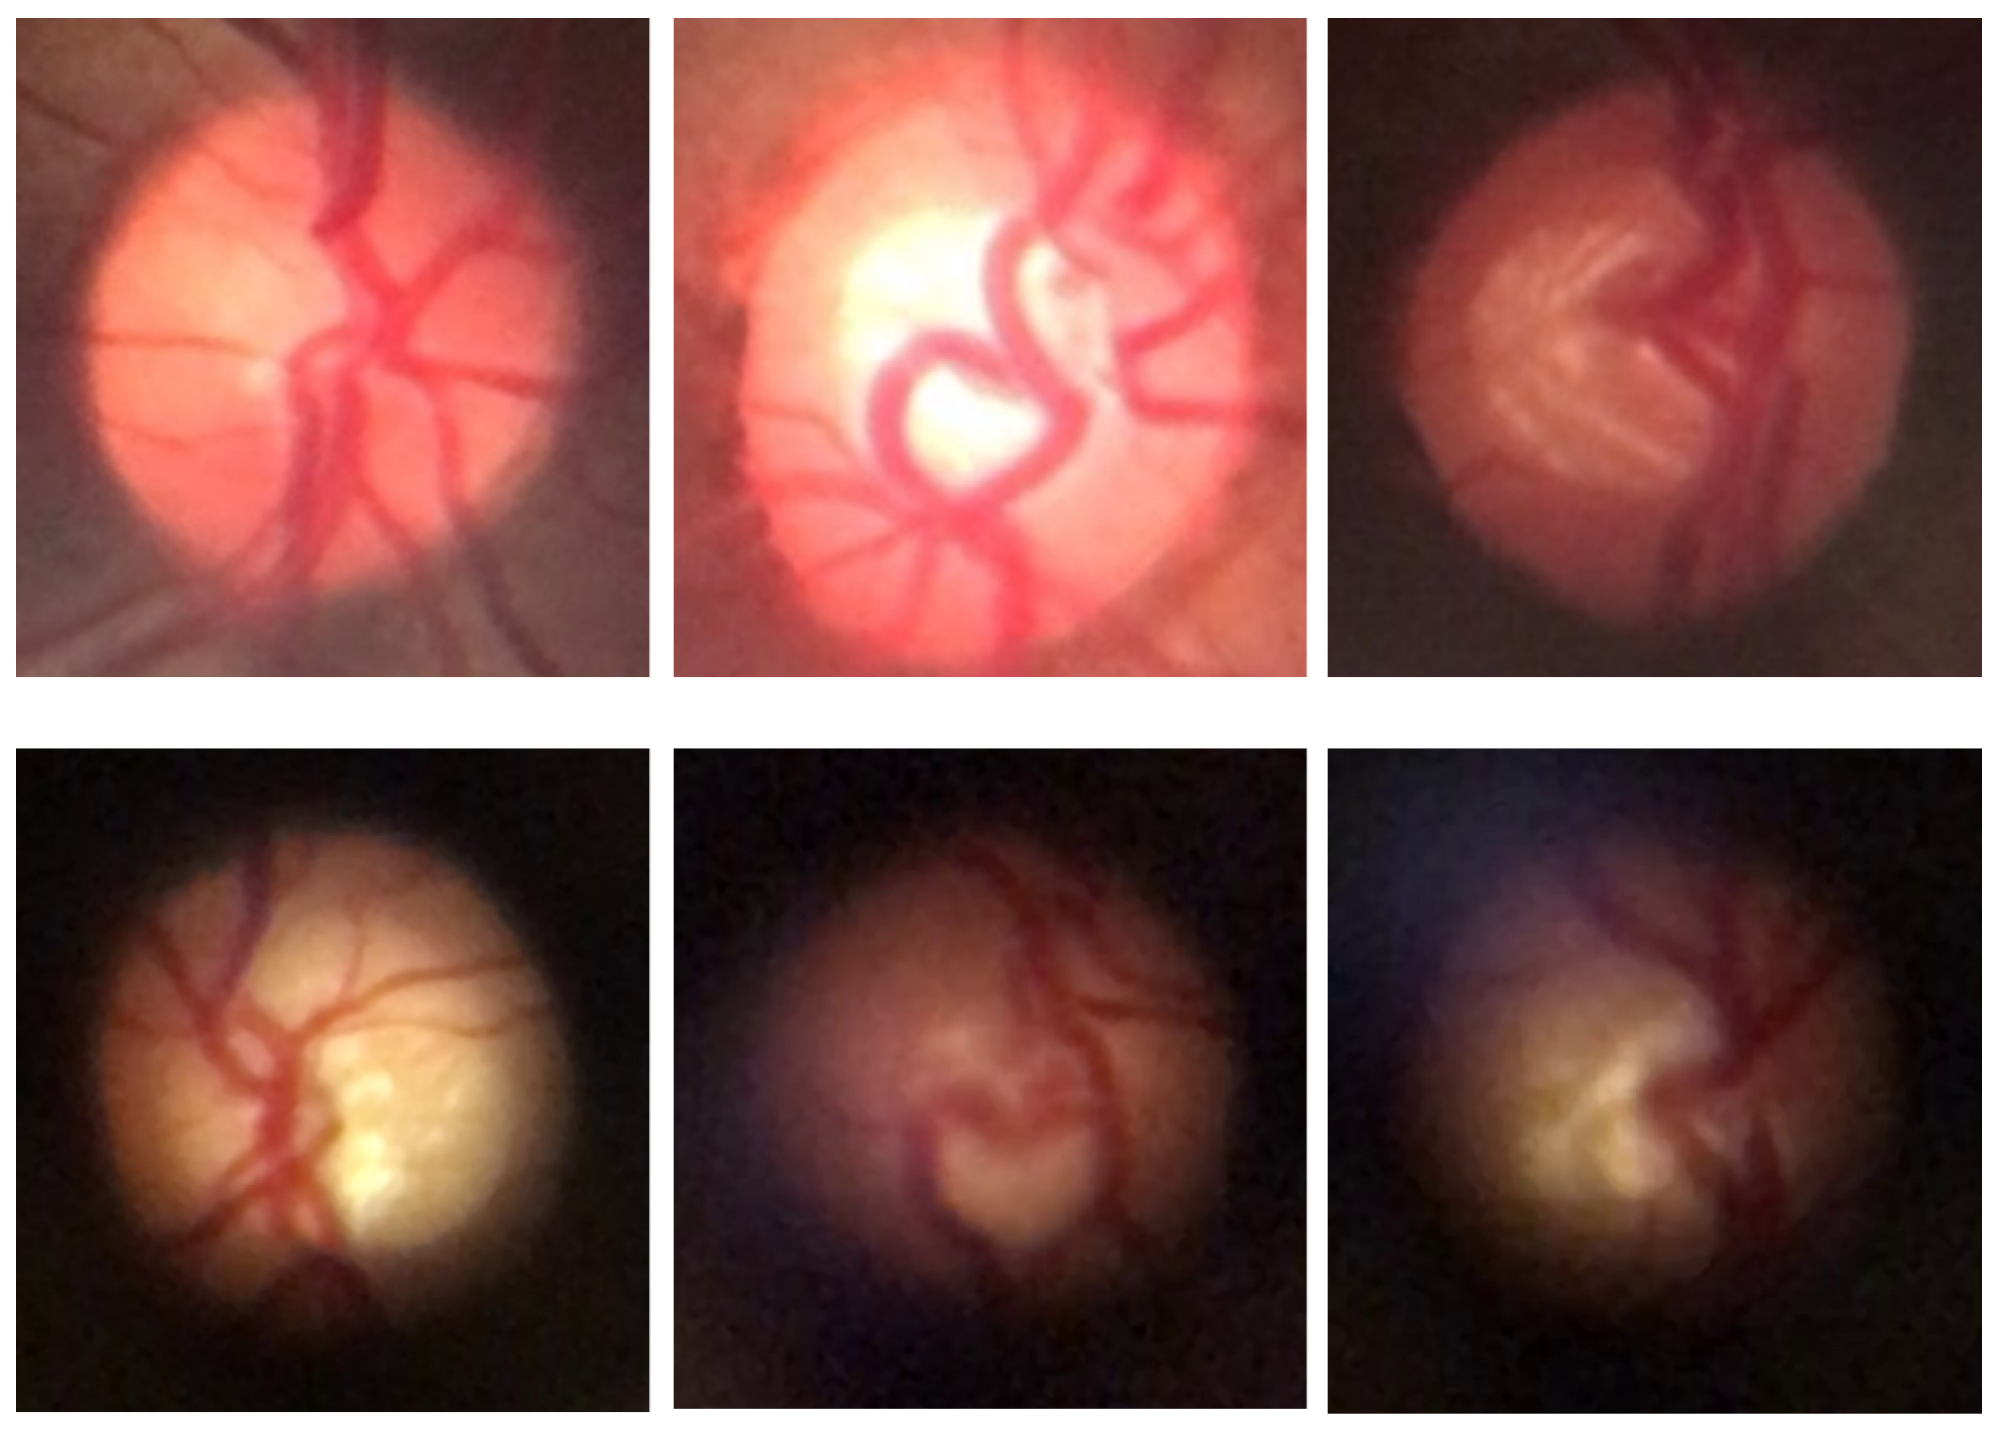

For subsequent processes, the BrG and D-Eye datasets were merged to form a combined dataset, allowing for the exploration of image diversity across different devices and capture conditions. Figure 4 shows examples of fundus images from both datasets, highlighting the distinctive characteristics of each set, such as resolution, field of view, and image quality.

Figure 4. Sample fundus images from the datasets used in this work. The first row shows images from the BrG dataset, while the second row displays images from the D-Eye dataset.